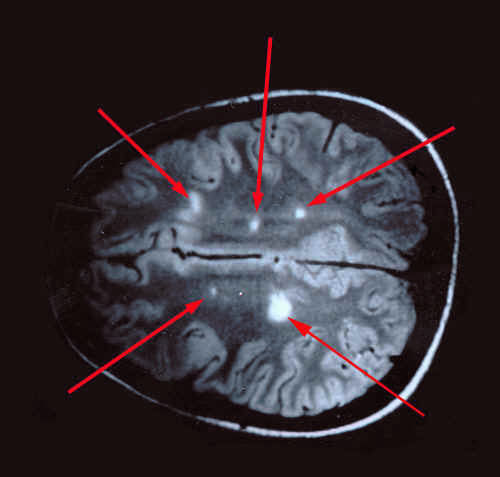

На МРТ круглые или овальные гиперинтенсивные очаги демиелинизации чаще всего выявляются в белом веществе под корковым слоем, вокруг желудочков мозга (перивентрикулярно). Они распределены диффузно и имеют разные размеры — от нескольких миллиметров до 2-3 см. Для уточнения времени появления очагов используется контрастное усиление: более «молодые» участки демиелинизации лучше накапливают контрастное вещество по сравнению с теми, которые существуют длительное время.

Заболевание обычно затрагивает несколько отделов нервной системы одновременно, включая головной и спинной мозг. Одной из характерных особенностей является наличие на МРТ бляшек различного возраста — от свежих до склерозированных. Это свидетельствует о хроническом воспалительном процессе и объясняет разнообразие симптомов, которые могут меняться по мере прогрессирования демиелинизации.